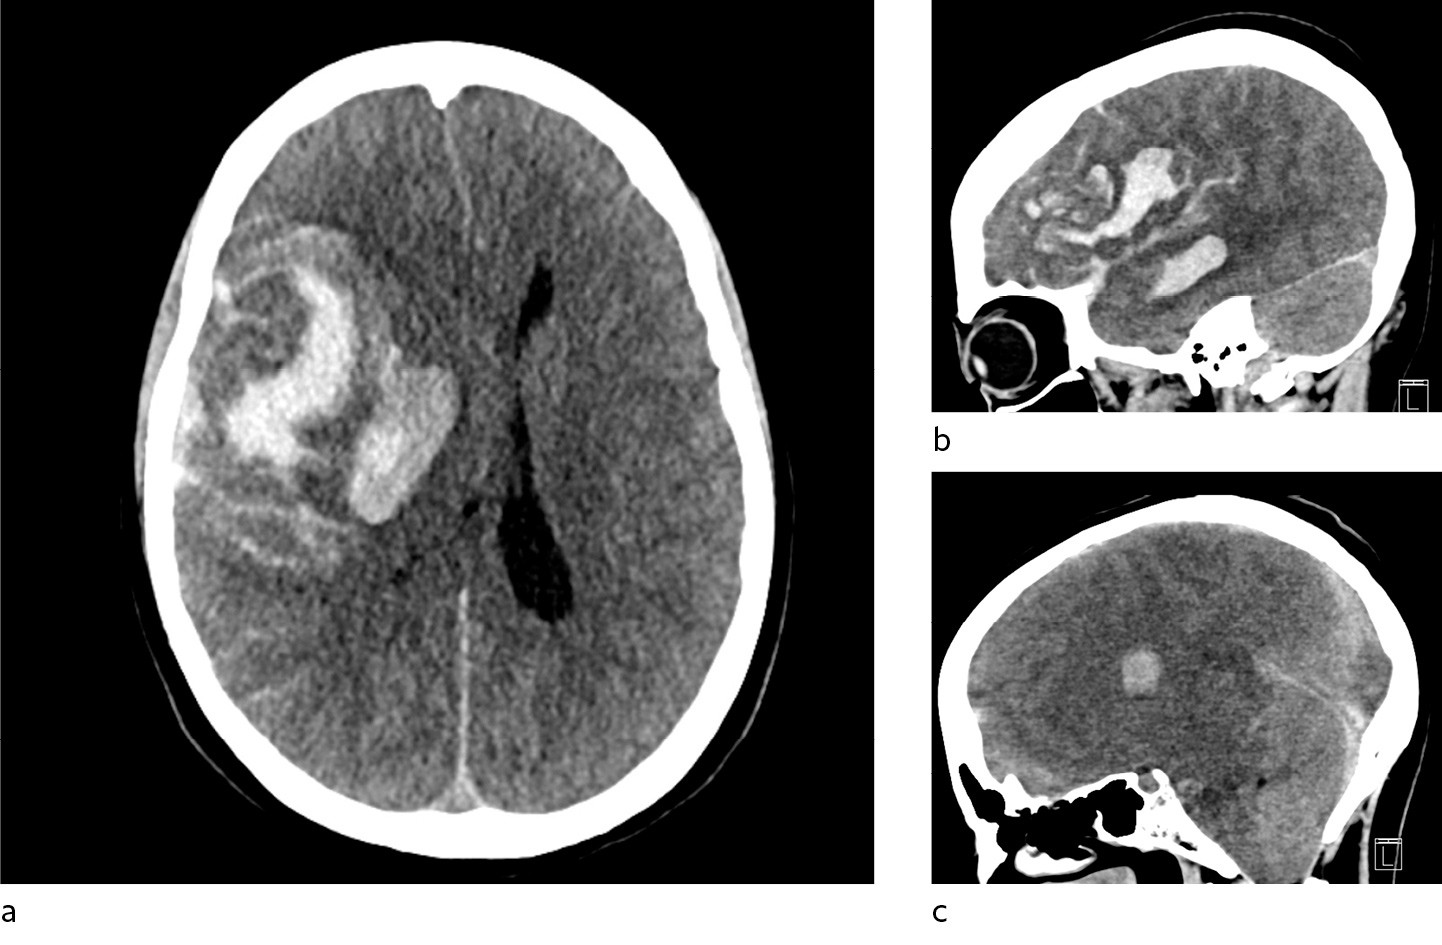

Pasienten ankom universitetssykehuset tre timer etter varsling fra lokalsykehuset. Ved mottak hadde pasienten bilateral mydriasis uten lysreaksjon. Behandling med mannitol ble igangsatt, og CT caput tatt umiddelbart etter ankomst viste progrediering av en stor intrakranial blødning med startende herniering (figur 2). Cerebral angiografi (TCD) var forenlig med opphørt blodsirkulasjon i hjernen, og videre tiltak ble vurdert som uhensiktsmessige.

Få dager etter denne hendelsen ble det meldt fra Rikshospitalet om flere tilfeller av alvorlige blodpropper og blødninger hos pasienter som hadde fått identisk vaksine. Også disse pasientene hadde lave trombocyttall, og i disse tilfellene klarte man å finne en sammenheng mellom hendelsene og vaksinen (1). Tilstanden er etter dette omtalt som vaksineindusert trombotisk trombocytopeni (VITT), som kjennetegnes av lave trombocyttall, trombedannelser og antistoff mot platefaktor 4 (1, 5). I lys av denne kunnskapen ble det gjort nye undersøkelser, og man fant også hos vår pasient tendens til trombedannelse med små tromber i sinus transversus, pannelapper og a. pulmonalis. Det ble også påvist antistoff mot platefaktor 4. Samlet sett er det derfor mye som taler for at dette var et tilfelle av vaksineindusert trombotisk trombocytopeni. Retrospektivt må man spørre seg om blødningen sett på CT representerte et venøst hemoragisk infarkt tilsvarende det som ble sett hos flere pasienter på Rikshospitalet (1), og om blødningskomponenten kan ha vært dominerende som følge av vaksineindusert trombotisk trombocytopeni. Et venøst infarkt kunne kanskje forklare pasientens hodepine.